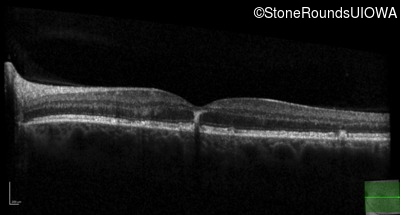

Optical Coherence Tomography - Left - 20/32 sc

Exemplar / OCT Stack